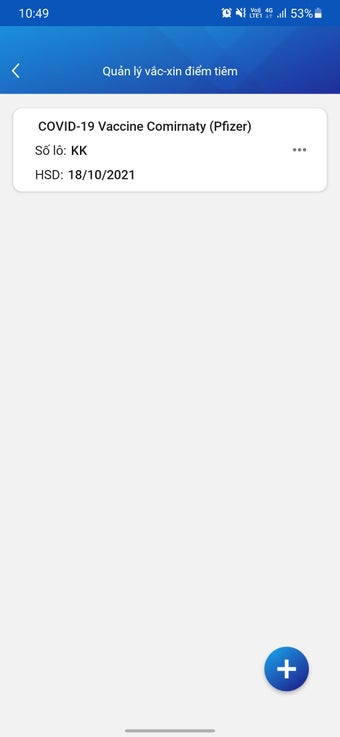

บันทึกข้อมูลสุขภาพอิเล็กทรอนิกส์สำหรับแพทย์เป็นแอปพลิเคชันแอนดรอยด์ที่พัฒนาโดย Văn phòng Bộ Y tế Việt Nam แอปพลิเคชันฟรีนี้ออกแบบมาเพื่อบุคลากรทางการแพทย์และแพทย์เพื่อเก็บข้อมูลผู้ป่วย ทำการฉีดวัคซีน เพื่อลดความแออัดที่จุดฉีดวัคซีน และลดความเสี่ยงในการติดเชื้อ COVID-19 นอกจากนี้ยังช่วยในการแก้ไขปัญหาสุขภาพของประชาชนอย่างรวดเร็ว

ด้วยบันทึกข้อมูลสุขภาพอิเล็กทรอนิกส์สำหรับแพทย์ บุคลากรทางการแพทย์สามารถวินิจฉัยและรักษาผู้ป่วยได้อย่างง่ายดาย โดยให้การดูแลสุขภาพอย่างครบถ้วนและต่อเนื่อง ตรวจจับโรคในระยะเริ่มต้น และให้การรักษาทันเวลา ซึ่งเป็นปัจจัยที่สำคัญในการเพิ่มประสิทธิภาพในการรักษาและลดค่าใช้จ่ายด้านสุขภาพสำหรับประชาชน